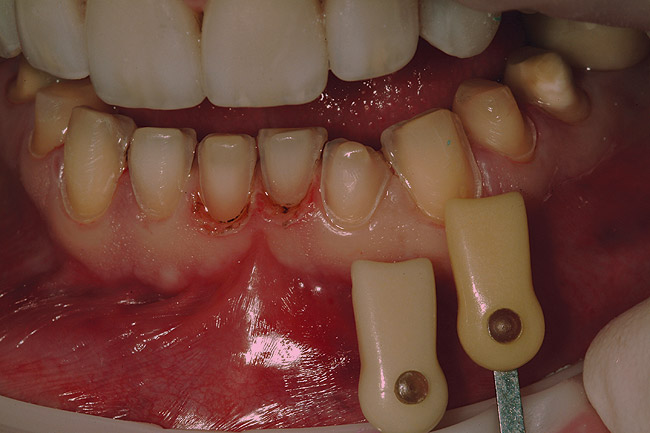

Figure 33  The colors of the lower anterior preparations were recorded by a shade comparison photograph.

Figure 33

Figure 34  After isolating the preparations from moisture using a latex-free rubber dam and blue mouse, the restorations were ready to be inserted.

Figure 34